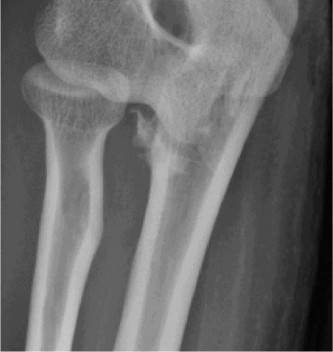

Treat a patient with scapular winging? CASE 23 A 47-year-old, right-hand-dominant male presents to your clinic complaining of right shoulder weakness for the past 2 months. He denies any history of trauma but notes sudden onset of pain 2 months ago that lasted approximately 2 weeks and then subsided without any intervention and was followed by shoulder weakness. He works as a lawyer and has been going through a divorce for the past year. Physical examination reveals no tenderness to palpation about the shoulder. He has decreased sensation over the lateral aspect of the shoulder, decreased muscle bulk over the left shoulder compared with the contralateral side, and weakness with left shoulder abduction. He is distally neurovascularly intact. The patient had already been referred for an x-ray and MRI by his primary care doctor that are shown in Figures 2–62 and 2–63.

Figure 2–62

Figure 2–63

The correct answer is (C). The patient’s decreased sensation over the deltoid, deltoid muscle atrophy on examination, and MRI with atrophy of the teres minor points to axillary nerve dysfunction. Suprascapular nerve injury (Choice A) would result in atrophy of the infraspinatus and or infraspinatus muscles, leading to weakness with external rotation and/or forward flexion. Dorsal scapular nerve injury (Choice B) would result in weakness of the rhomboid muscles and levator scapulae. While injury to the posterior cord of the brachial plexus (Choice D) would result in symptoms of axillary nerve palsy, they would also involve dysfunction of the radial nerve, which also comes off the posterior cord.

The correct answer is (B). Parsonage Turner syndrome (brachial neuritis) is characterized by acute brachial neuropathy which can affect different nerves of the brachial plexus. In this patient, it is the most likely explanation for his atraumatic deltoid paralysis with axillary nerve palsy in a time of severe stress. The cause of Parsonage Turner Syndrome is unknown, but it has been associated with severe stress and viral infection. Quadrilateral space syndrome (Choice A) involves entrapment of the axillary nerve as it passes through the quadrilateral space, would present as chronic dull pain, and is usually not associated with decreased sensation. While Choices C and D can both be a cause of axillary nerve injury, the patient has no history of trauma and there are no masses on his MRI.